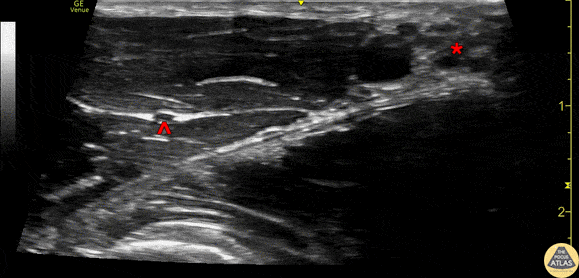

Demonstration of the axillary brachial plexus as seen in transverse view with the linear transducer at the level of the proximal humerus. The brachial plexus (*) can be seen medial to the pulsating axillary artery. The musculocutaneous nerve (^) can be seen lateral to the artery/brachial plexus, deep to the biceps muscle and superficial to the coracobrachialis muscle. Drs. Sam Paskin-Flerlage, PGY4 and Michael Heffler, PGY3 Denver Health Residency in Emergency Medicine